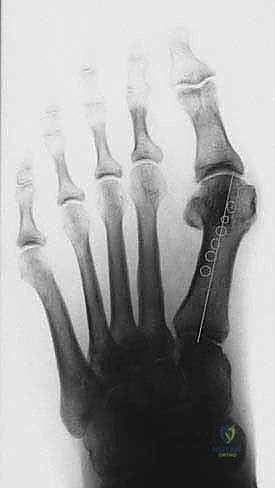

الخطوة الرابعة: إعادة التوجيه والتثبيت الداخلي

بعد قص العظم، يتم تحريك الجزء البعيد (الذي يحمل المفصل والإصبع) نحو الخارج لتصحيح التشوه وتضييق المسافة بين الأمشاط. بمجرد الوصول للوضع المثالي، يتم تثبيت العظمين معاً بقوة باستخدام برغيين أو ثلاثة من التيتانيوم الطبي عالي الجودة. هذه البراغي تدفن داخل العظم ولا تحتاج للإزالة لاحقاً.

الخطوة الخامسة: الإغلاق التجميلي

بعد التأكد من استقرار العظم ووضعه المثالي (غالباً باستخدام جهاز أشعة سينية داخل غرف العمليات Fluoroscopy)، يتم إزالة النتوء العظمي المتبقي. أخيراً، تُغلق الكبسولة المفصلية والجلد بخياطة تجميلية دقيقة لتقليل الندبات، وتوضع ضمادات ضاغطة خاصة.